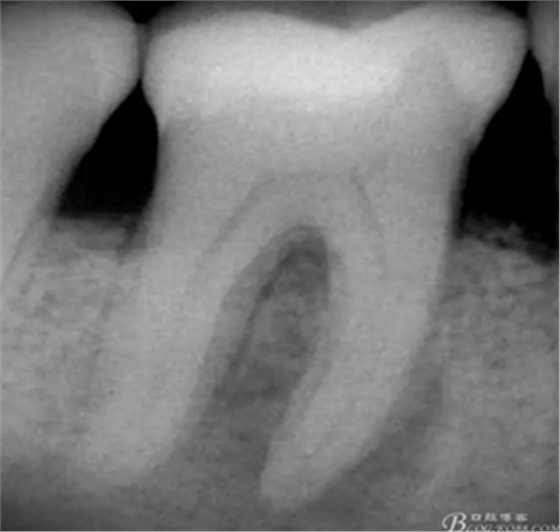

術(shù)前X片

高嵌體粘固后X片